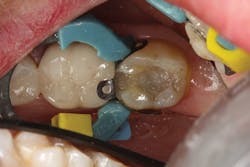

The difference in using this product over standard- or non-bulk-fill composites comes in the filling technique. The manufacturer states that you can predictably cure an increment of this composite up to 4 mm in depth. This assumes the light energy coming from your curing light is ideally positioned and is functioning properly (power intensity of 1000 mW/cm2 or greater). For carious lesions that are relatively small to moderate in size (figures 1a and 1b), this translates, in general, to being able to place one increment of composite that fills partway up the proximal box to the level of the contact and onto the occlusal pulpal floor (figure 2). The second increment could then be placed on top, which would fill the rest of the restoration.